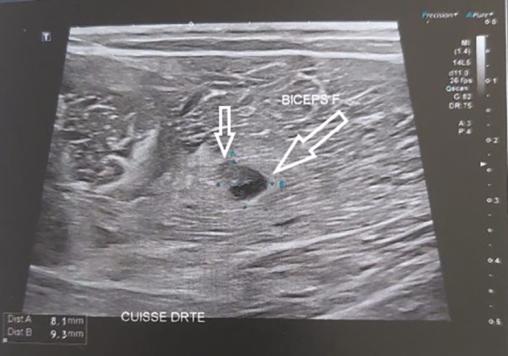

Un patient de 40 ans se présente quarante-huit heures après un traumatisme musculaire indirect. Lors d’une accélération en jouant au football, il a ressenti une vive douleur au niveau des ischio-jambiers. Il n’a pas pu terminer le match. À l’examen, l’ecchymose est superficielle, non localisée au niveau de la douleur initiale (fig. 1 ). Il existe une douleur à la palpation et à la contraction des ischio-jambiers, sans déficit moteur. L’échographie montre deux déchirures du biceps fémoral avec deux petits hématomes (fig. 2 ). Le traitement a associé glaçage, repos, contention et kinésithérapie précoce.